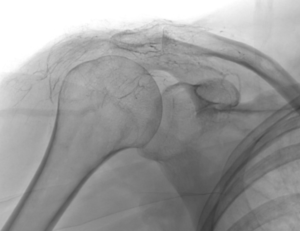

L’embolisation de la capsulite rétractile est une innovation récente qui cible la cause profonde de l’inflammation : l’hypervascularisation. Dans une épaule gelée, de petites artères anormales se développent autour de la capsule, alimentant le processus inflammatoire et la douleur.

Grâce à l’imagerie de précision (angiographie), le radiologue interventionnel identifie ces vaisseaux « anormaux » et les occlut sélectivement. En bloquant leur flux sanguin, on réduit l’apport en oxygène et nutriments à la zone enflammée, favorisant une résolution rapide des symptômes.